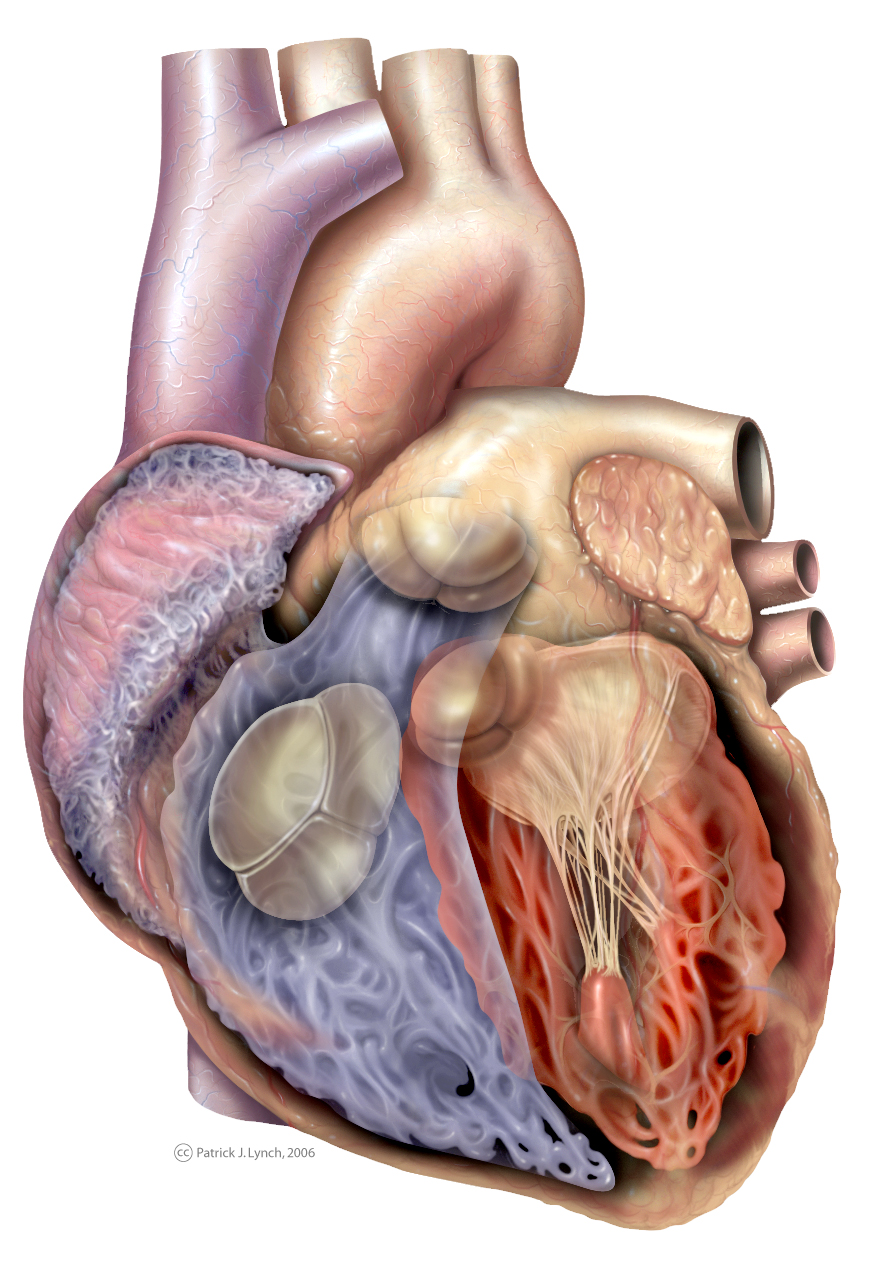

//thebrainstormlab.com/banners/ami_banner.jpgThis is a medical | Heart anatomy drawing, Human  Human Heart Section 3D model | CGTrader

Human Heart Section 3D model | CGTrader  human heart - internal anatomy 3d model

human heart - internal anatomy 3d model  3D Illustration Human Heart 3D Images - Iwish Iwas

3D dissected human heart model - TurboSquid 1361664  10 Realistic Heart Drawings and Tattoos â Simple Human Heart Sketch for 2022 | Do It Before Me

Human Heart Section 3D model | CGTrader  3d human heart

Human Heart Cutaway Anatomy 3D model section | CGTrader  Human Heart by Mutantenmaid on DeviantArt

human heart interior 3d model  Image of Human Heart 3D Illustration | Stock Image MXI28575

3d human heart section  human heart solidworks 3d model

human heart - internal anatomy 3d model  Heart Diagram Human Heart Images Hd 3D - img-Badr